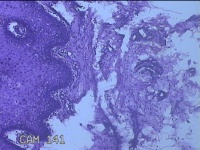

右下唇肿物

性别

女

年龄

12岁

临床诊断

唇囊肿

一般病史

右下唇部肿物一月余。

标本名称

大体所见

灰白粉红色肿物0.8x0.7x0.2cm一个,表面光滑。

图4